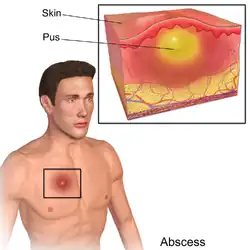

Абсце́сс (лат. abscessus — нарыв) — гнойное воспаление тканей с их расплавлением и образованием гнойной полости, может развиться в подкожной клетчатке, мышцах, костях, а также в органах или между ними. Абсцесс может возникать как самостоятельно (фурункул), так и являться осложнением другого заболевания (пневмония, травма, ангина — паратонзиллярный абсцесс).

Развитие абсцесса связано с попаданием в организм гноеродных микробов через повреждения кожи или слизистых оболочек или с заносом возбудителя по кровеносным и лимфатическим сосудам из другого гнойного очага. Защитная реакция организма проявляется в образовании капсулы, ограничивающей абсцесс от здоровых тканей.

При локализации абсцесса в поверхностных тканях всегда имеются все 5 классических симптомов воспаления:

- покраснение

- припухание

- повышение температуры

- болезненность

- расстройство функции

Основным признаком абсцесса является симптом флюктуации.